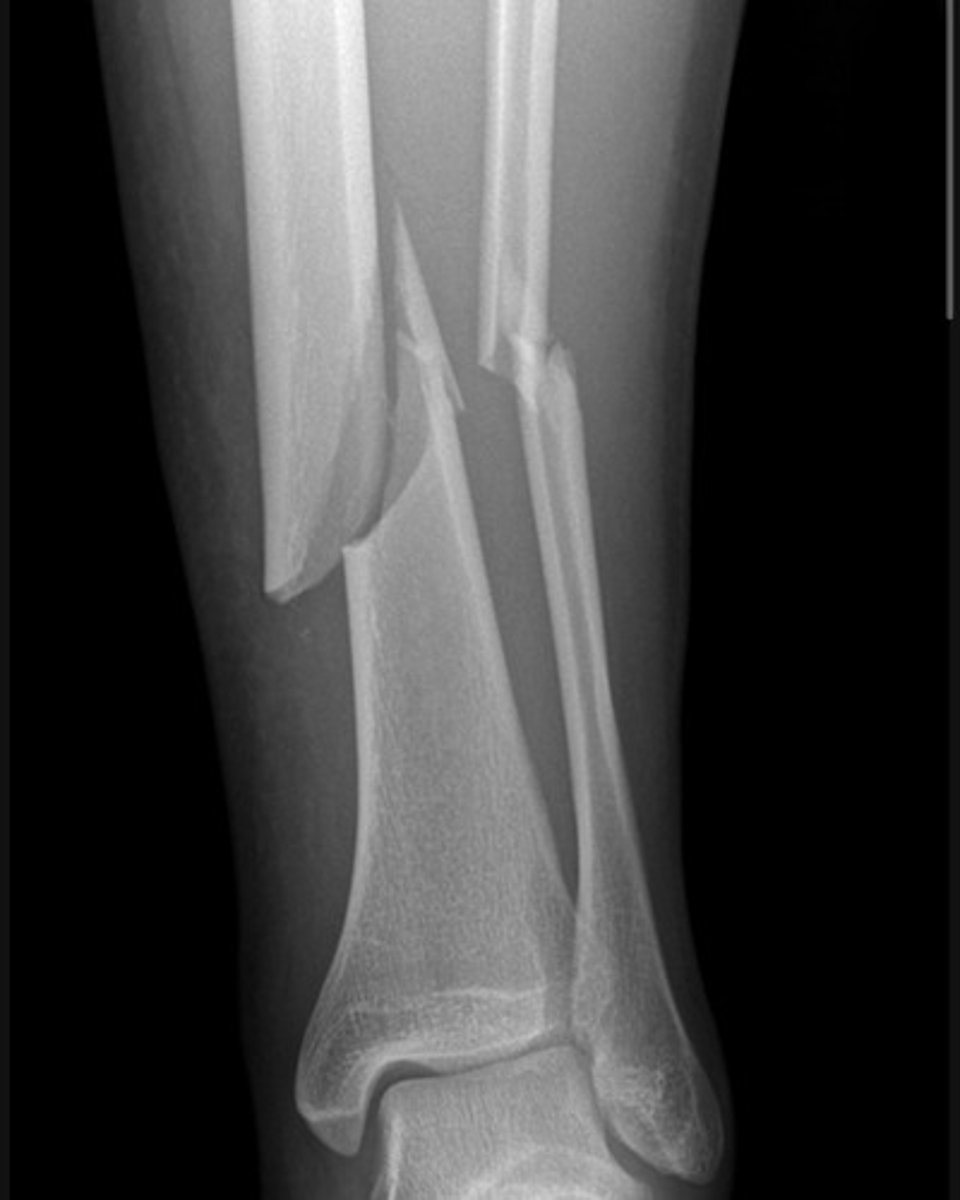

There are complete fractures involving the distal third diaphyses of both the tibia and fibula. The tibial fracture is oblique. The distal tibial fragment is laterally displaced and angulated relative to the proximal shaft. The fibula demonstrates an associated oblique fracture with mild displacement.